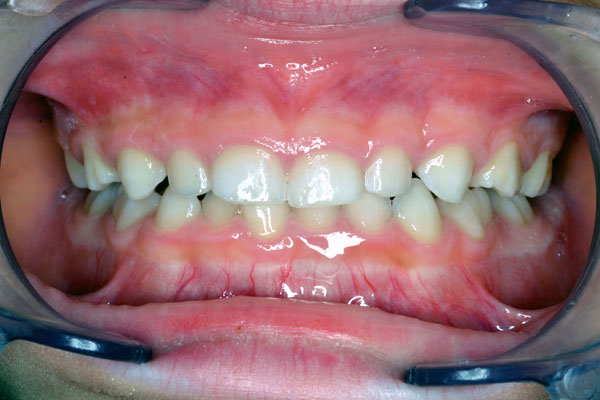

受け口は治りましたが、デコボコしています。仕上げに前歯だけにブレースとワイヤーを装着します。11才2ヶ月です。

1期矯正の完成です。お母様の熱意の賜物です。ご希望のご家族は2期矯正に進みます。13才0ヶ月でした。歯並び育成期間6年11ヶ月です。